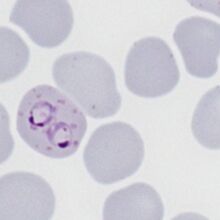

The schizont

The schizont is the asexual form of the malaria parasite that will circulate in blood in most species, but is an uncommon feature in P.falciparum:

- Do not generally circulate in this species consider causes

- The merozoites cluster "untidily" but may be numerous (8-16+ when mature)

- In this species the loose pigment may be seen in clumps between the parasites

- Red cell size is generally unaffected but red cells become pale as haemoglobin is metabolised by the parasites

P.falciparum schizonts